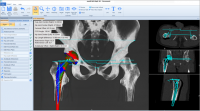

Phần mềm MediCAD dự đoán chính xác kích thước trên 90%, giảm rủi ro cho bệnh nhân và giảm chi phí nhiều trong quá trình phẫu thuật, điều trị các bệnh về xương, khớp háng, hông, đùi.

Giao diện của Phần mềm MediCAD dễ hiểu, rõ ràng, dễ thao tác. Các bác sĩ có thể tập trung, phóng to các bộ phận quan trọng trong việc lên kế hoạch điều trị bệnh.